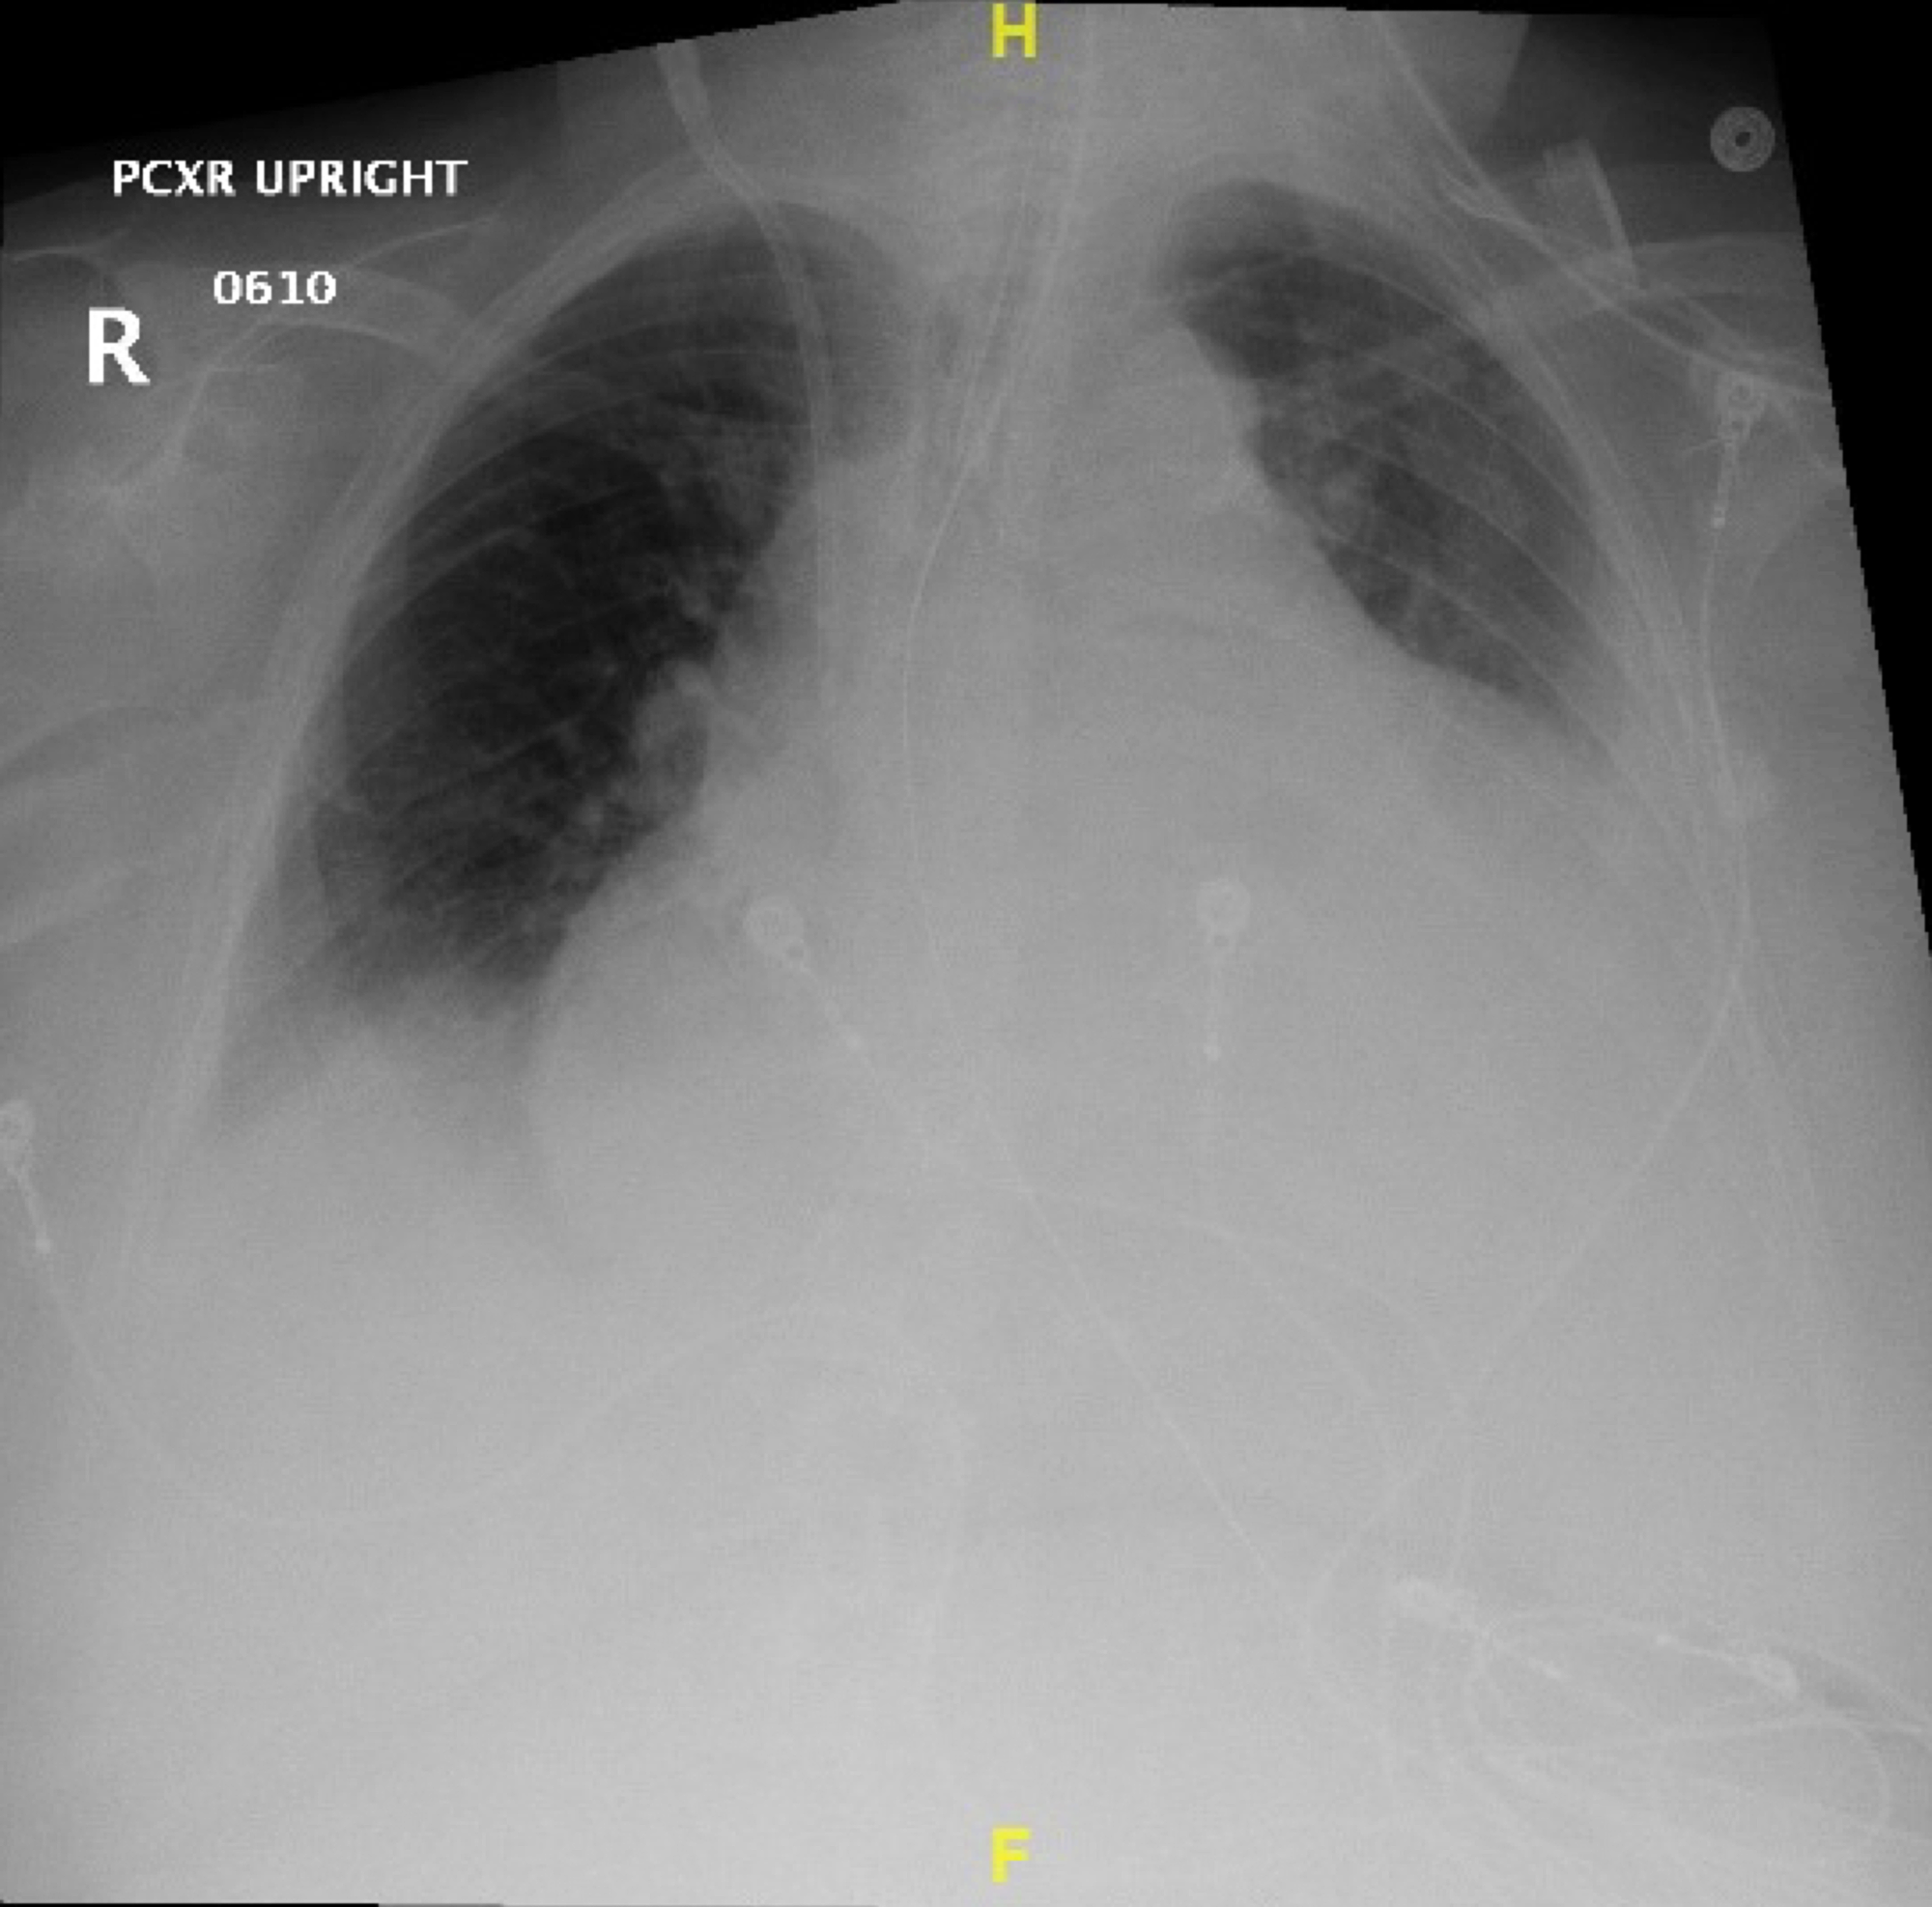

Chest Xray upon admission. Cardiomegaly, pulmonary edema, and Chest X-Ray To Diagnose Leukemia Although the thorax is uncommonly involved, it may occur in the lungs, pleura, mediastinum, chest. — myeloid sarcoma. a ct scan of the chest or abdomen can help detect an enlarged lymph node or cancers in the liver, pancreas, lungs, bones and. — physical exams for diagnosing leukemia. Consider seeking medical care if you have developed any. Chest X-Ray To Diagnose Leukemia.

Cureus Impending Cardiac Tamponade as the Initial Manifestation of Chest X-Ray To Diagnose Leukemia a ct scan of the chest or abdomen can help detect an enlarged lymph node or cancers in the liver, pancreas, lungs, bones and. It is used to look for: Although the thorax is uncommonly involved, it may occur in the lungs, pleura, mediastinum, chest. — myeloid sarcoma. Consider seeking medical care if you have developed any of. Chest X-Ray To Diagnose Leukemia.

Cureus Concurrent Diagnosis of Acute Myeloid Leukemia and COVID19 A Chest X-Ray To Diagnose Leukemia It is used to look for: — myeloid sarcoma. — physical exams for diagnosing leukemia. If the scan finds an abnormal. Consider seeking medical care if you have developed any of these. Although the thorax is uncommonly involved, it may occur in the lungs, pleura, mediastinum, chest. a ct scan of the chest or abdomen can help. Chest X-Ray To Diagnose Leukemia.

Cureus STElevation Myocardial Infarction in a 56YearOld Man With Chest X-Ray To Diagnose Leukemia Consider seeking medical care if you have developed any of these. It is used to look for: If the scan finds an abnormal. Although the thorax is uncommonly involved, it may occur in the lungs, pleura, mediastinum, chest. — physical exams for diagnosing leukemia. a ct scan of the chest or abdomen can help detect an enlarged lymph. Chest X-Ray To Diagnose Leukemia.

Pulmonary edema A four year old girl with sepsis and leukemia. The Chest X-Ray To Diagnose Leukemia Consider seeking medical care if you have developed any of these. — myeloid sarcoma. — physical exams for diagnosing leukemia. If the scan finds an abnormal. It is used to look for: a ct scan of the chest or abdomen can help detect an enlarged lymph node or cancers in the liver, pancreas, lungs, bones and. Although. Chest X-Ray To Diagnose Leukemia.